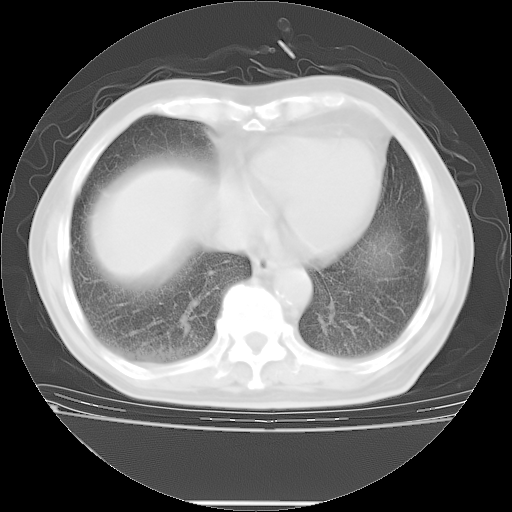

胸腹部CT,诊断意见:左上肺叶钙化灶、左侧胸膜局限性增厚并钙化、胆囊炎。描述部分肺组织呈磨玻璃样改变。